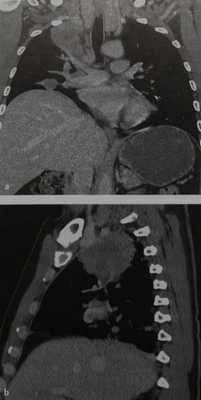

Опухоль Панкоста у мужчины 43 лет. На корональном (а) и сагиттальном (b) срезах видна крупная опухоль верхушки правого легкого, инфильтрирующая средостение и диафрагмальный нерв. О вовлечении диафрагмального нерва в опухолевый процесс говорит высокое стояние купола диафрагмы на стороне поражения. Опухоль имеет широкую поверхность соприкосновения с плеврой.